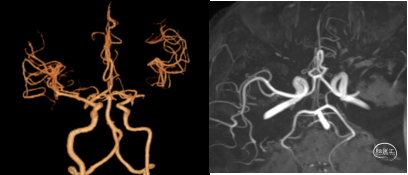

(三)、影像评估 术前血管影像评估

明确责任大血管: ICA、ACA 的 A1 段、MCA 的 M1、M2 段、VA 的 V1~V4 段、BA、PCA的P1段为直径2mm以上的血管为大血管,病变往往症状较重。

明确病因:血栓?夹层?其他?确定弓上血管的入路路径,为血管内治疗选择适合技术方案提供参考。

评估方法:CTA和MRA能够看到直径1mm以下的血管。CTA能够显示闭塞远端代偿充盈的血管全貌。